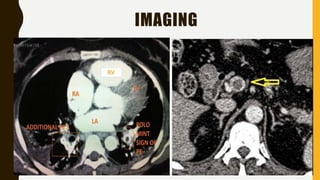

IMAGING

• CT pulmonary angiography (CTPA) will show filling defects

within the pulmonary vasculature with acute pulmonary emboli.

• When the artery is viewed in its axial plane the central filling

defect from the thrombus is surrounded by a thin rim of

contrast, which has been called the Polo Mint sign.

RV